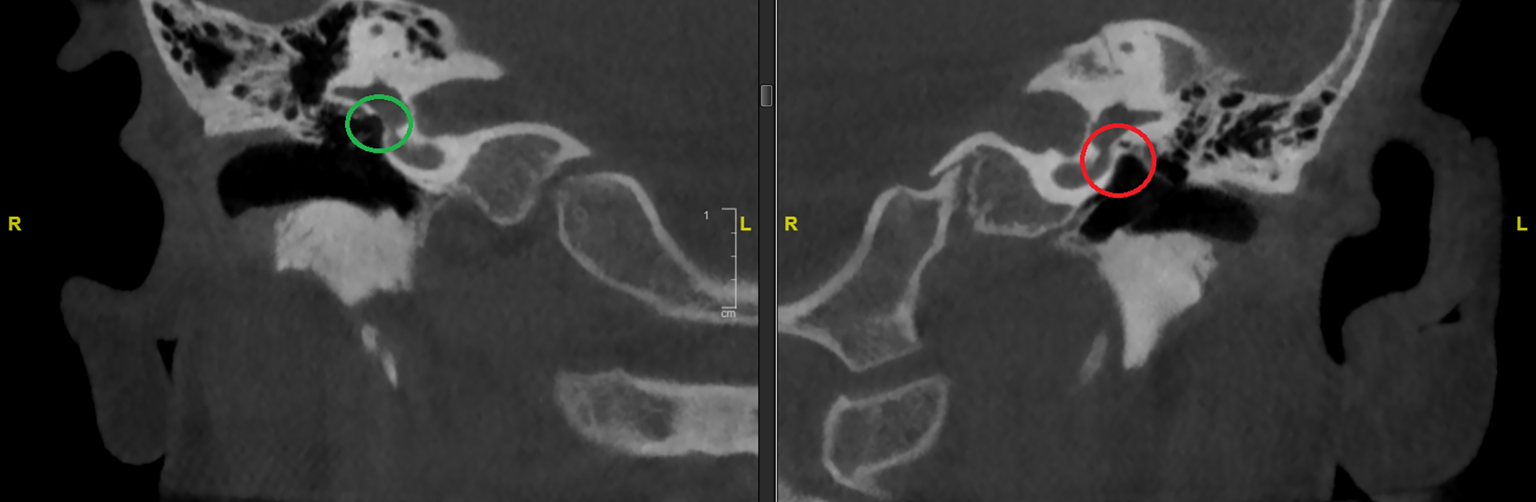

Eine weiterführende radiologische Abklärung mittels Feinschicht-CT des Felsenbeins kann aufgrund mangelnder Konsequenz bis zum Alter von 4–6 Jahren zurückgestellt werden [7]. Hierdurch ist eine Einschätzung bezüglich der Ausprägung sowie eine endgültige Einordnung der Fehlbildung von Gehörgang und Mittelohrstrukturen möglich. Eine entsprechende Diagnostik sollte nur dann durchgeführt werden, wenn daraus eine entsprechende Konsequenz resultiert. Durch die Kenntnis eingangs dargestellter embryologischer Entwicklung kann eine Schichtbildgebung in bestimmten Fällen vermieden werden. Indiziert ist eine solche Untersuchung bei Schallleitungsblöcken unklarer Genese oder klinisch diagnostizierten Gehörgangsatresien (Abb. 7).

Abb. 7

Axiale Schichten der Felsenbein-Computertomographie eines 6‑jährigen Patienten mit rechtsseitig nicht sondierbarem Gehörgangslumen, knöcherne Gehörgangsatresie (roter Kreis). Diesbezüglich Normalbefund auf der Gegenseite (grüner Kreis). (Quelle: eigenes Bild des Autors)